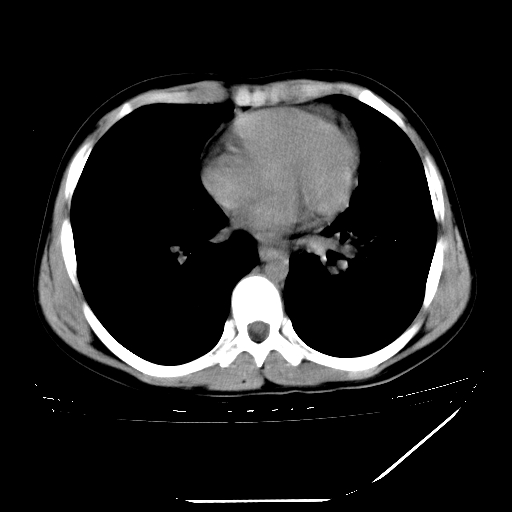

男,13岁,咳嗽、咳痰伴发热一周。

上纵隔课件多枚淋巴结,部分相互融合,左侧支气管壁增厚,肺纹理较右侧增粗,患者,男,13岁,

中上纵隔见多枚淋巴结肿大,部分相互融合成团片,左肺门增大,上叶支气管变窄,肺内多处斑片状 索条状及棉絮状致密影。临床“男,13岁,咳嗽、咳痰伴发热一周。”首先考虑:原发综合征!不除外淋巴瘤可能!

纵隔多发肿大淋巴结,部份有融合改变。双肺血管气管束增厚,以肺门为中心向外周散发,以左肺下叶为明显。考虑淋巴瘤可能性大。不除外原发综合征。

中上纵隔见多枚淋巴结肿大,部分相互融合成团片,左肺门增大,上叶支气管变窄,左肺支气管血管束增粗,可见磨玻璃样影。临床“男,13岁,咳嗽、咳痰伴发热一周。”首先考虑:淋巴瘤可能性大!

中上纵隔见多枚淋巴结肿大,部分相互融合成团片,纵隔内脂肪间隙模糊,左肺门增大,上叶支气管变窄,左肺支气管血管束增粗,可见磨玻璃样影。考虑纵隔淋巴管炎